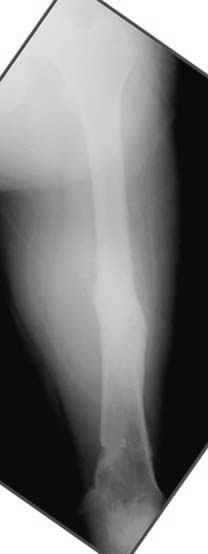

Несколько снимков из моей коллекции, чтобы разьяснить, почему мы до сих пор делаем различные варианты остеотомии.

На рисунке N1 предоперационный план лечения ложного сустава шейки бедра- линия ложного сустава, угол и направление введения импланта, клиновидная остеотомия в градусах и миллиметрах, второй снимок после коррекции, расчет, на сколько удлиняется конечность и размеры импланта;

N3 рисунок окончательный снимок, после операции моя рентгенограмма должен выглядеть примерно как эта картина. На N4 снимке клин перед удалением; N5 послеоперации 3 нед.; N6 окончательная рентгенограмма.

пластическая модель; и коррекция бедра аппаратом Илизарова.